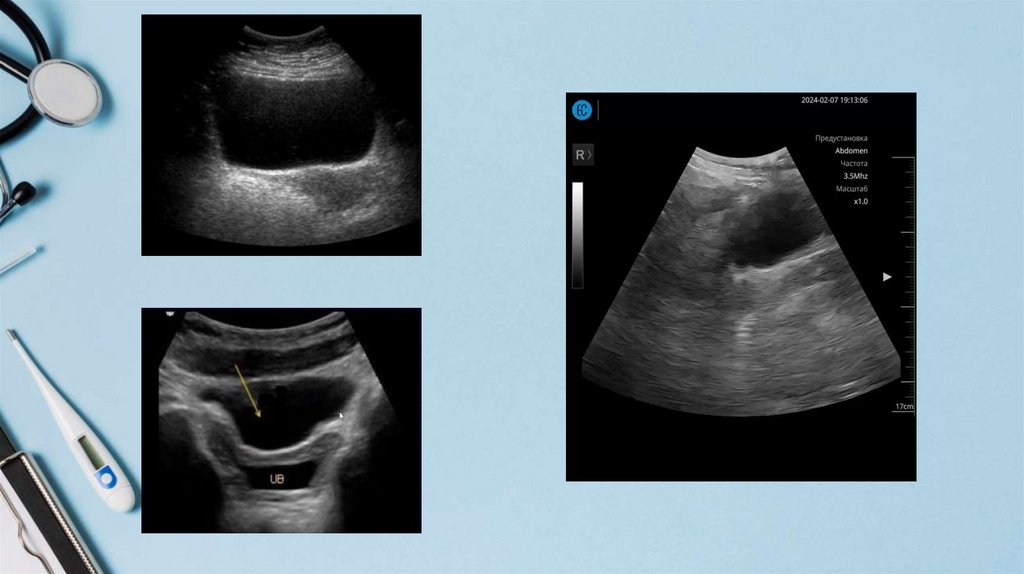

поиск НПВ (субкостальный доступ)

Пресеты:

1) Режим «Брюшная полость (Abdomen)»

2) Настройка минимального усиления (параметр GAIN)

3) Глубина не более 10-13 см